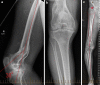

Multiple acceptable options are available for the correction of distal femoral deformity associated with knee arthritis. The treatment modality should be chosen based on the extent of deformity and attention to preservation of the collateral ligaments. Surgical options range from osteotomy alone, arthroplasty with intra-articular correction, or arthroplasty with extra-articular correction. Different implant choices and fixation methods for the osteotomy possess advantages and disadvantages which need to be considered carefully. In addition to discussing principles of management based on current literature, this article includes a case report using a previously undescribed technique using corrective osteotomy, intramedullary nail fixation, and total knee arthroplasty with computer navigation.